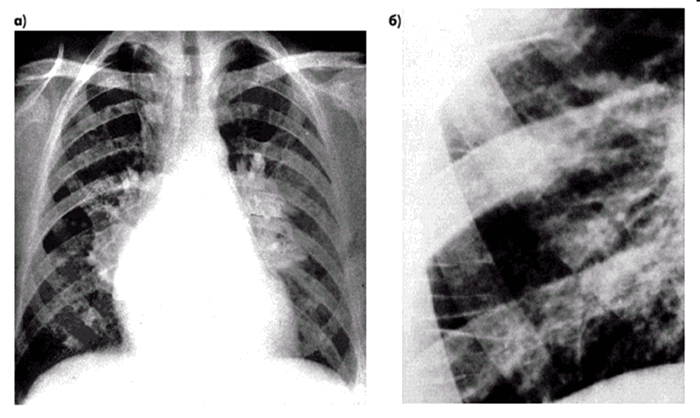

- R-графия легких: снижение прозрачности, субплевральный отек. «Крылья бабочки», диффузные или фокусные изменения;

На картинке представлено, как жидкость затопляет альвеолы. Отек легкого начинает развиваться с нижних отделов.